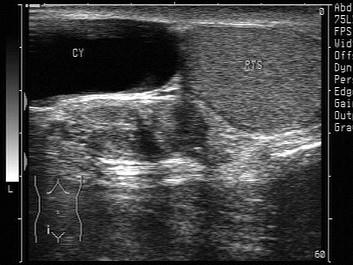

问题 鞘膜积液分四种,如图所示为哪种?(?)

选项 A.睾丸鞘膜积液 B.精索鞘膜积液 C.睾丸精索鞘膜积液 D.交通性鞘膜积液 E.以上都不是

答案 B